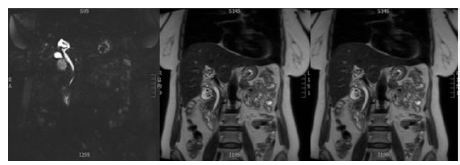

Case Report: A 58-year-old asymptomatic female was referred to the General Surgery clinic following an incidental finding of thyroid nodules on imaging. She had no significant personal or family history of thyroid disease. Routine blood and thyroid function studies were within normal limits. Neck ultrasound demonstrated a multinodular goiter with a hypoechoic nodule in the right superior thyroid. Fine needle aspirate (FNA) showed atypia of unknown significance (Bethesda 3). She underwent a right hemithyroidectomy which confirmed on pathological examination to be a 19 mm intrathyroidal paraganglioma, which was positive for neuroendocrine markers and negative for calcitonin and cytokeratin. Serum metanephrine studies returned within normal limits.